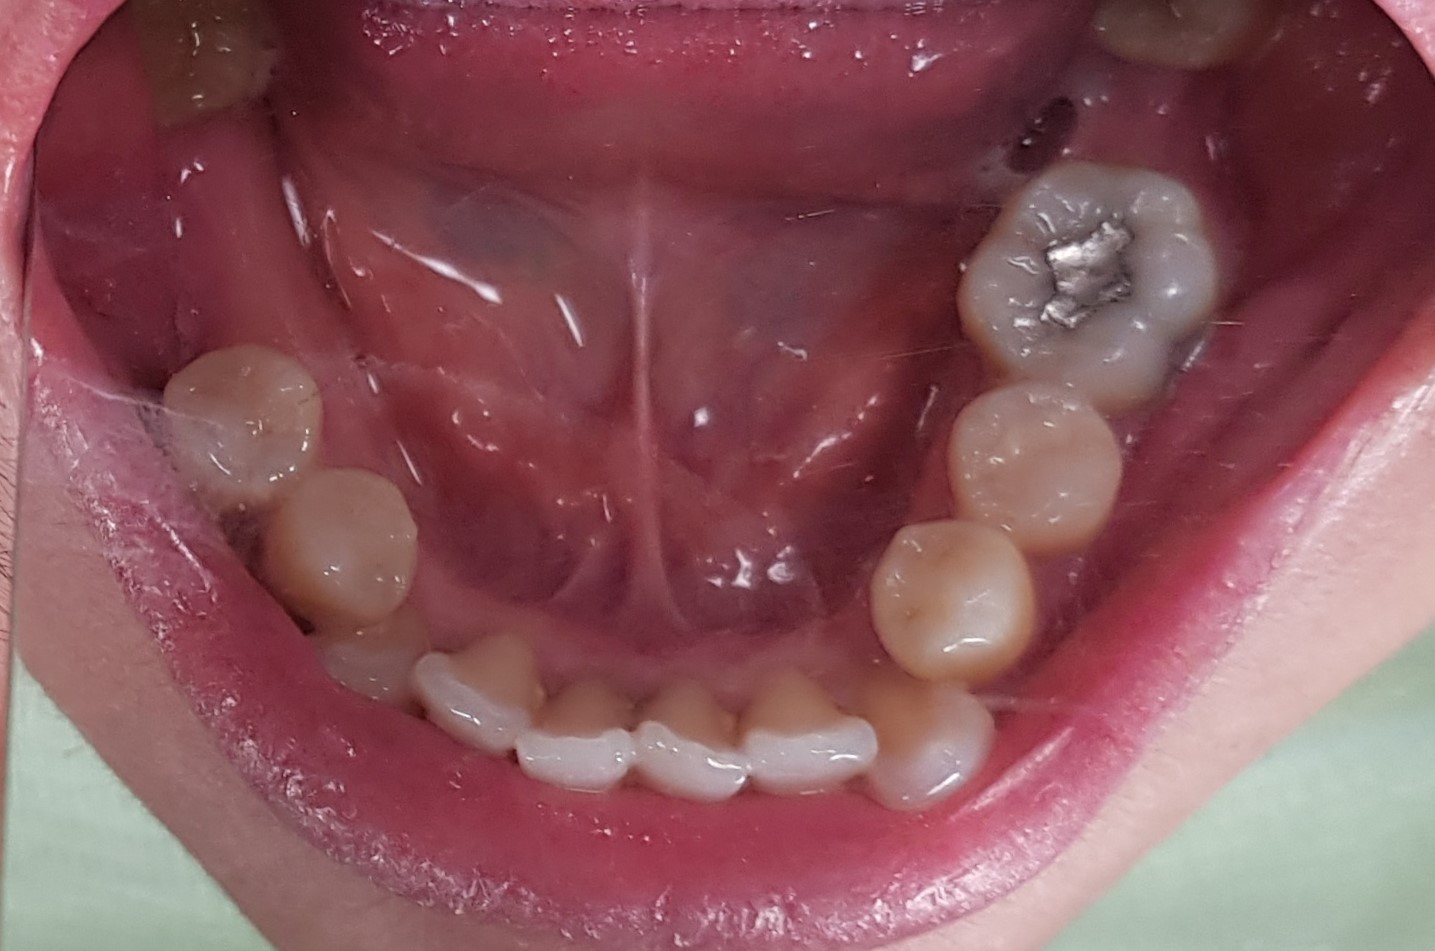

Abstract: Removable partial denture is a definitive prosthesis that has been used in dentistry for decades for the rehabilitation of partially edentulous patients. The visibility of the retentive arm in the metal denture sometimes causes esthetic problems for the patient. Therefore, aesthetic aspects should be considered to ensure patient satisfaction in dental treatment. This case report described oral rehabilitation using a combination of metal frame partial denture and thermo-plastic. A 40-year-old female patient with a history of old removable partial denture came to replace the old denture with a new one that was more aesthetic and showed no wire. The management of the patient included thorough anamnesis, extra and intra oral examinations, anatomic impression, determination of definitive treatment, preparation of rest on the abutment tooth, physiological impression, manufacturing of metal frameworks in the upper and lower jaws, determination of definitive vertical dimension, try-in denture, insertion, and control of combination of a metal frame partial denture with thermoplastic in the upper and lower jaws. The patient was satisfied with her new denture.  In conclusion, the combination of a metal frame partial denture with thermoplastic can be an alternative treatment for patient who wants to replace his/her missing teeth with removable partial denture while still prioritizing aesthetic factors.